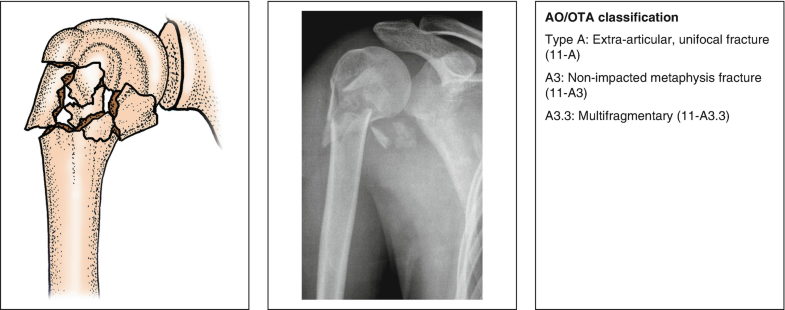

OTA Classification • 3 Main Types • Extraarticular fracture (13AX) • Partial articular fracture (13BX) • Complete articular fracture (13CX) • Each broad category further subdivided into 9 Proximal Humerus AO Classfication – www2aofoundationorg AO/OTA Classification Based on fracture location and the presence of impaction, angulation, translation, comminution, or dislocation;